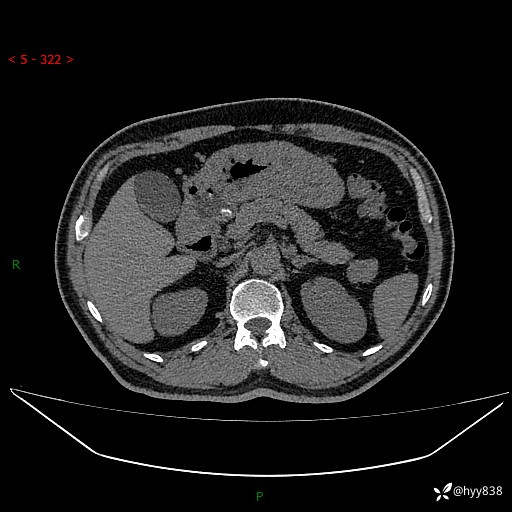

讨论:病变性质?

静脉期